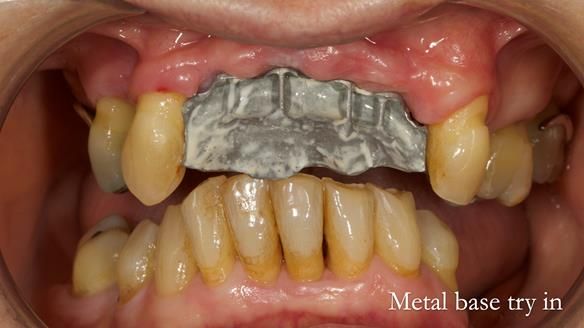

In this edition, I present the removable partial denture treatment for Jean, an 80-year-old woman with a sore mouth caused by a soft tissue-supported 'gum stripper' acrylic denture and a clenching habit. Below, I outline the step-by-step process of her treatment. It wasn't straightforward; I had to remake the denture after it fractured to achieve a satisfactory result. Each patient is unique, and sometimes a new RPD serves as a prototype. Occasionally, I need to make adjustments, learn from any mistakes, and refine the design to get it right.

The treatment has been a success over the past 4 years.